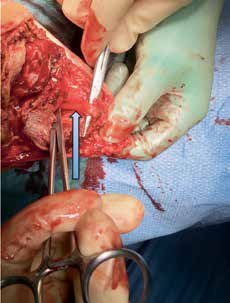

Alle durchtrennten Nerven bilden nach einer Amputation als typische Spätkomplikation ein Neurom. Unzählige Techniken und Technologien wurden entwickelt und vorgeschlagen, um Neuromen und deren akuten Folgen vorzubeugen. Keine dieser Techniken konnte zeigen, dass sie der konventionellen einfachen Neurotomie überlegen ist, wenn der Operateur bei der Amputation einige wichtige Faktoren beachtet. Dazu zählen die ausreichende Kürzung des Nerven und dessen Einbettung in eine gut gepolsterte Region. Die Einbettung erfolgt meistens in die Muskulatur, in der der Nerv vor Druck und mechanischer Irritation geschützt ist. Werden Nerven nicht ausreichend gekürzt und/oder in eine gut gepolsterte Region gelegt, dann liegen sie knapp unter der Haut und teilweise auf dem Knochen, sodass sie stark elektrisierende Schmerzen verursachen und eine Prothesenversorgung teilweise unmöglich machen können. Der N. suralis ist sicherlich mit am häufigsten von o. g. Komplikationen betroffen, da er leider immer wieder bei der Unterschenkelamputation im wahrsten Sinne des Wortes „vergessen“ wird zu versorgen (Abb. 2). Wendet man dann noch die Burgess-Technik an, kommt der Nerv direkt am vorderen tibialen knöchernen Stumpfende zu liegen und wächst meistens in die Hautnarbe ein, mit konsekutiver Ausbildung starker elektrisierender Schmerzen.